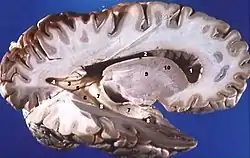

Brain size

Early research into the differences between male and female brains showed that male brains are, on average, larger than female brains. This research was frequently cited to support the assertion that women are less intelligent than men.[71][73] One of the most influential early researchers on this topic was Paul Broca. In 1861, he examined 432 human brains from cadavers and found that the brains of males had an average weight of 1325 grams, while the brains of females had an average weight of 1144 grams. This study, however, did not control for differences in body size or age.[73][74] Later studies have shown that while male's brains are an average of 10-15% larger and heavier than female's brains, there is relatively no difference when controlling for body weight. This means the brain-to-body mass ratio is, on average, approximately the same for both sexes.[71][73] Comparing a male and a female of the same body size, an average difference of 100 grams in brain-mass is present, the male having the bigger and heavier brain. This difference of 100 grams applies over the whole range of human sizes.[75][76]